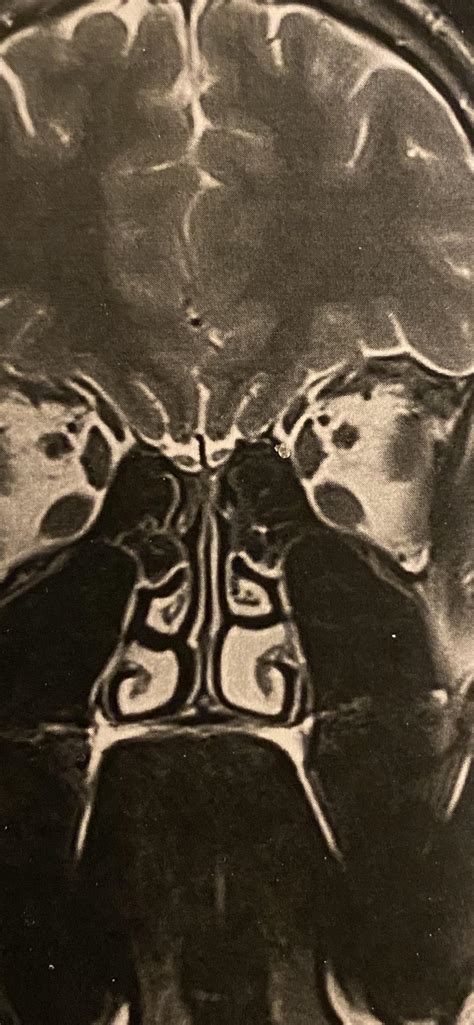

When you examine clinical documentation or Enlarged Turbinate Ikon, the deviation between a healthy rhinal transition and one regard by hypertrophy is quite stark. A healthy airway typically has a open, visible gap between the turbinate and the nasal septum, allowing air to legislate freely. In a hypertrophic province, the turbinal tissue swells to the point where it may touch the septum or the floor of the nasal cavity.

notably that these picture are oftentimes taken during a nasal endoscopy, a subprogram where an ENT specialist utilize a thin, flexible tube with a camera to get a open view of the internal nasal construction. If you are live persistent symptom, relying solely on internet icon can be deceptive, as anatomic fluctuation are mutual. A professional physical examination is necessary to correlate what you see in those image with your own symptom.